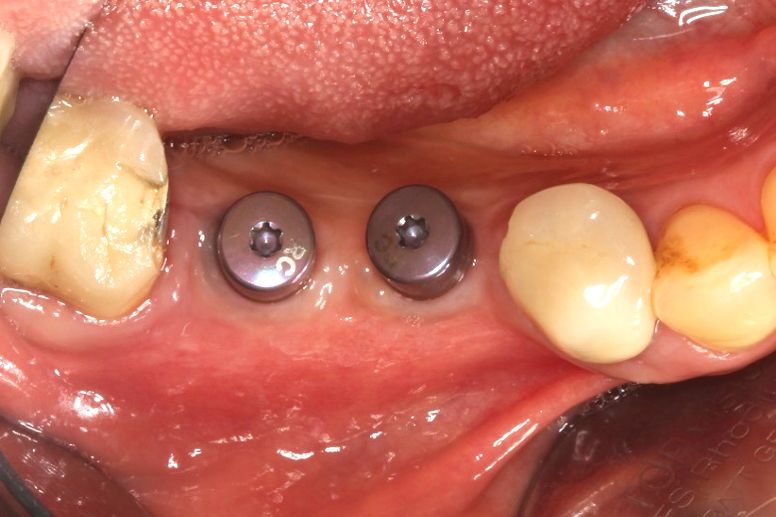

Following 5 months of uneventful healing, the patient presented for the next procedure, which included the insertion of two fixed dental implants and simultaneous soft tissue thickening (Fig. 13). The previously placed incision lines were reopened in order to remove the titanium osteosynthesis screws used for cortical strut fixation (Fig. 14). Vital, bleeding and robust bone was found within the granule-filled space adjacent to the avital cortical strut, which was flush-mounted in the new formed bone tissue (Fig. 15). Horizontal bone gain was sufficient for stable and fully submerged implantation of the designated Straumann BLT implants with a torque value of 35 Ncm (Figs. 16-17). Subsequently, cover screws were inserted in the implants, and bone substance, which was being removed during placement of the pilot drill, was used for contouring around the implant shoulders (Fig. 18). Prior to wound closure, which was performed with double-sling sutures, a porcine collagen matrix (botiss mucoderm®) was placed over the augmentation site to thicken the soft tissue (Figs. 19-20). A radiographic control image was recorded in order to assess implant position and bone density within the augmented area (Fig. 21).

Following 3 months of healing, the thickened soft tissue presented a natural and healthy appearance, so that papilla shaping could be achieved by the installation of gingival formers to set the course for a positive aesthetic final outcome (Figs. 22-23). Well-conditioned soft tissue was found 5 weeks later when the gingiva formers were removed and the final prosthetic restoration was installed (Fig. 24).